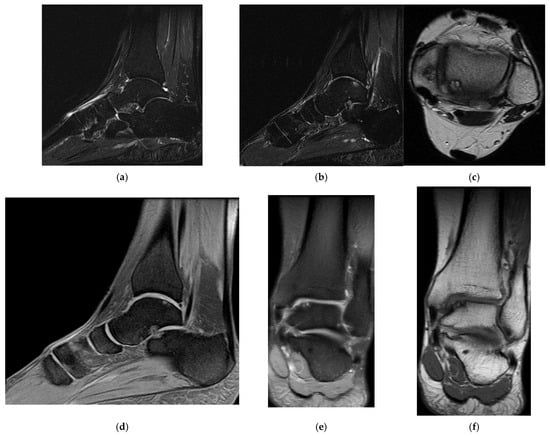

3.4. Case 4: Type III Accessory Navicular Impingement

A 26-year-old goalkeeper with a navicular injury, boasting six years of experience as a first-league professional in Romania, hails from an urban area and stands at 192 cm, weighing 95 kg. The latest case involves this goalkeeper, who, after sustaining a direct contact trauma during a match, reports experiencing pain and swelling in the dorsal part of his right forefoot. Forefoot X-ray diagnoses an improperly healed old right navicular fracture. As there was no trauma of the right foot, an MRI was performed, confirming the diagnosis of type III accessory navicular bone with impingement on the posterior tibial tendon.

Ankle MRI showed a well-delimited oval formation, at the posterior part of the navicular, with similar signals to the latter in T1 and T2 ponderations (bone formation), establishing certainty diagnosis of accessory navicular bone, excluding the suspicion of improperly consolidated navicular fracture/pseudoarthritis. STIR and PD fat sat sequences reveal hypersignal alterations in the posterior tibial tendon tangent to the accessory bone mentioned above, establishing the diagnosis of impingement syndrome with subsequent tendinopathy alterations (Figure 9, Figure 10 and Figure 11).

Figure 9.

(a) Ankle MRI: sagittal stir acquisition, (b) ankle MRI: sagittal stir acquisition, (c) ankle MRI: axial T2 acquisition, (d) ankle MRI: sagittal T2 fat sat acquisition, (e) ankle MRI: coronal PD fat sat acquisition, (f) ankle MRI: coronal T1.

Figure 10.

(a) Ankle MRI: axial T2 acquisition, (b) ankle MRI: axial T2 acquisition, (c) ankle MRI axial T2 acquisition.

Figure 11.

Ankle MRI: sagittal T2 fat sat acquisition.

Excluding the improperly healed fracture of the navicular, the patient was treated as a contusion with functional rest, NSAIDs, analgesics, and physical therapy, which allowed the player to recover early and resume his competitive activity after 1 week.